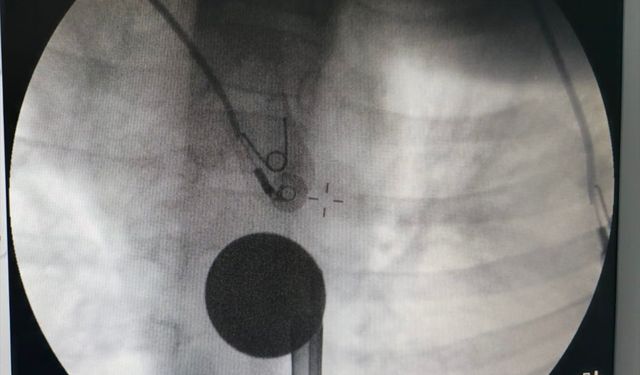

Siirt'te çocuğun boğazına kaçan madeni para çıkarıldı